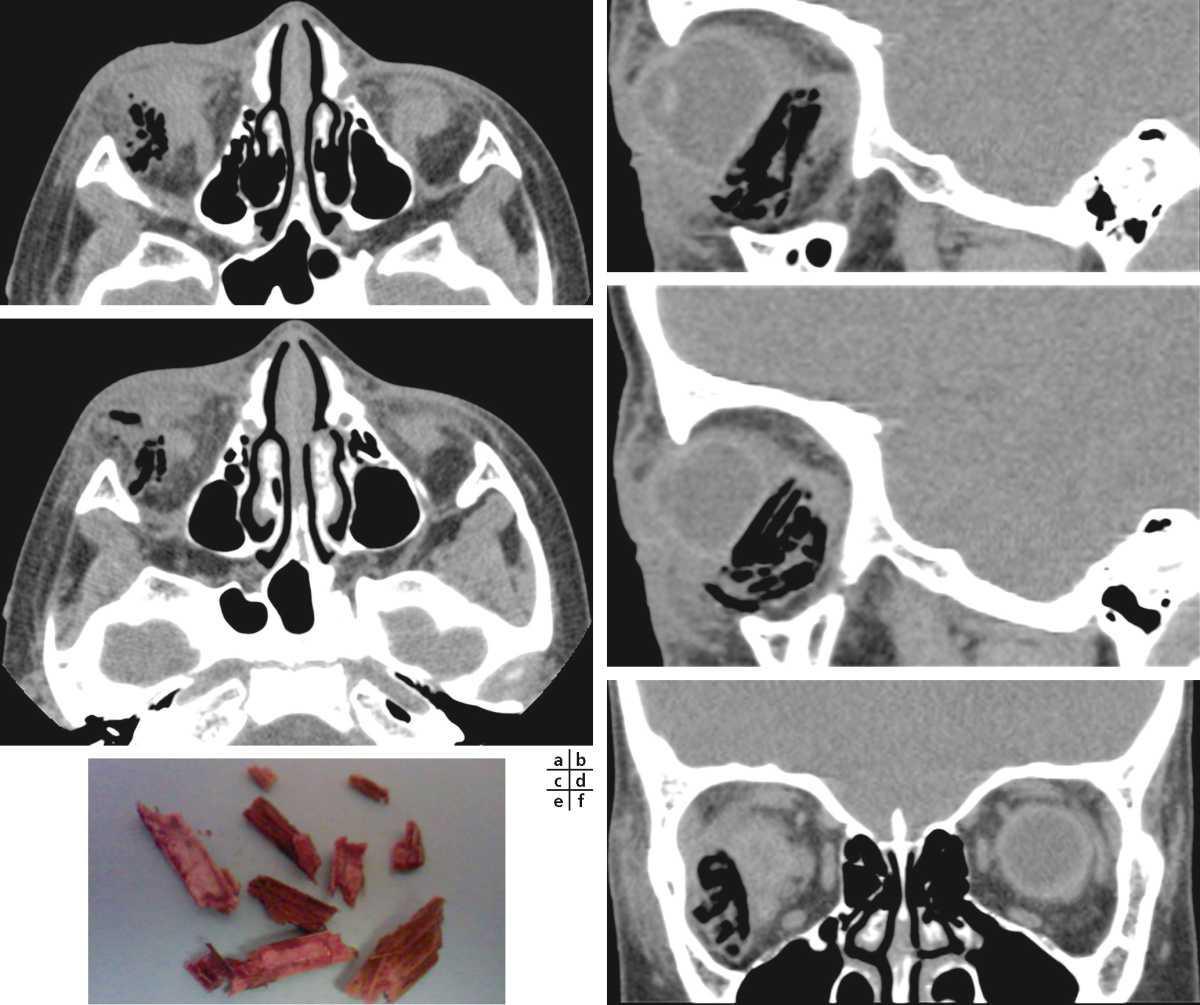

Les traumatismes avec plaie du globe et les corps étrangers peuvent être uniques ou multiples, comme dans le criblage facial avec des localisations oculo-orbitaires mais aussi à distance sur le scalp ou le cou. Le bilan comporte en plus des coupes natives, en fenêtre osseuse et parenchymateuse, des reconstructions dans les deux plans de l'espace, ainsi qu'un traitement volumique. Le scanner met toujours en évidence le corps étranger métallique, minéral et même végétal. La sensibilité et la spécificité sont élevées.

Le corps étranger se traduit au scanner par une hyperdensité millimétrique en fonction de la taille de la lésion générant souvent des artéfacts de calcul. La taille est souvent approximative à cause des mêmes artéfacts (fig. 6-2-58). Les localisations intra- ou parasclérales peuvent être difficiles à discerner. Un corps étranger mobile rend sa localisation difficile. Dans les situations de criblage, les corps étrangers métalliques sont retrouvés en intra-orbitaire, au niveau du massif facial, et parfois en intracrânien.

Scanner à rayons X : corps étranger intra-orbitaire (a, c, d, f, g, i), intra-oculaire (e), conjonctival inférieur (b), hémorragie vitréenne (h).

Le corps étranger végétal doit être recherché après orientation clinique. Le bois sec, hypodense au début du traumatisme, se réhydrate, devient isodense dans les heures qui suivent le traumatisme (fig. 6-2-59).

Scanner à rayons X : corps étranger végétal intra-orbitaire droit caractérisé par des hypodensités spontanées régulières (a, b, c, d, f), pièce opératoire (e).